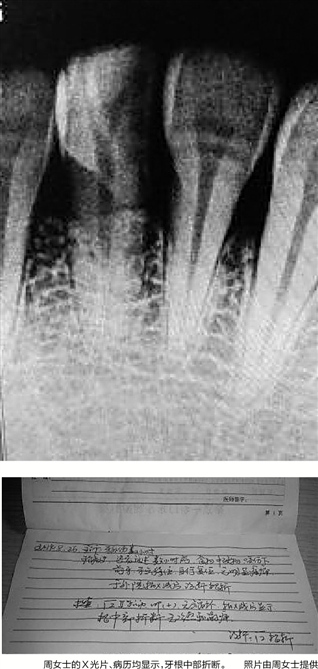

周女士按医生要求给牙齿拍了片。几个小时过去,医生综合检查情况给出了意见:第一,患者的牙齿总体健康,未见明显虫牙;第二,牙齿的牢固度良好,牙根较深;第三,牙齿受伤后留下的并非斜裂伤,而是横断面伤。诊断结果定性为:牙根中部折断。

“医生当时就说,这颗牙齿没有修复的可能性,只能拔除后重新种植。医生当时的建议是先拔牙,待3个月后再进行种牙,费用估计为1.5~2万元。”周女士只向单位请了4天的假就要返沪,她当面问肯德基工作人员该怎么办,对方答不上来。